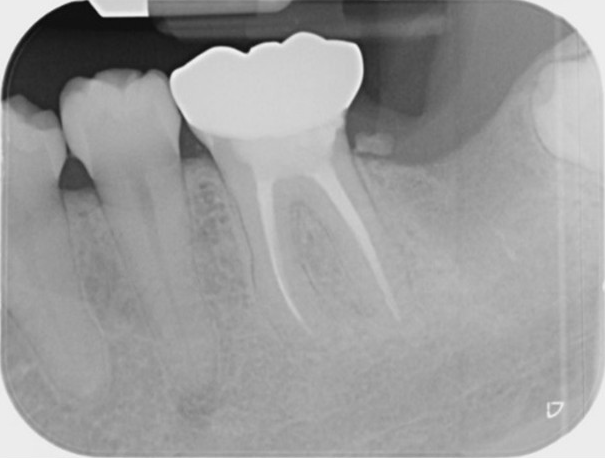

Molar endodontics

Pre-operative

Post-operative